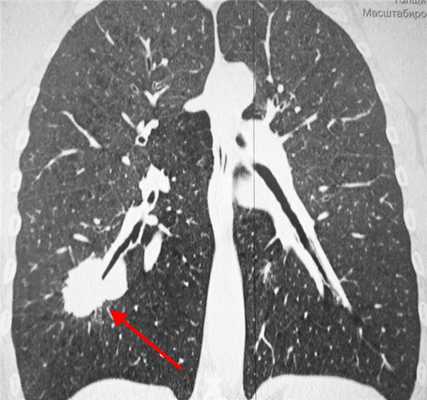

У пациента был выявлен раковый узел в 6 сегменте нижней доли слева. После резекции путем гистологического исследования верифицирован плоскоклеточный рак легкого. Томография в данном случае не дала типичную картину злокачественного новообразования.

2) Плоскоклеточный неороговевающий рак - часто встречающийся вариант - до 35% всех случаев образований легких. Характеризуется наилучшим прогнозом, редко метастазирует. Примерно в 65% развивается в одном из центральных бронхов и обуславливает картину ателектаза на КТ и рентгеновских снимках, в 35% развивается в периферических бронхах и выглядит как солидный единичный узел, часто с полостью распада в центре, похожий на абсцесс.

Типичный периферический рак легкого (аденокарцинома) на МСКТ. Справа в 6 сегменте легкого выявлен плотный мягкотканный узел со спикулами, деформирующий и подтягивающий к себе междолевую плевру.

Периферический рак легких на КТ выглядит как очаг либо узел, расположенный на периферии органа вдалеке от корня. Обычно он имеет однородную структуру, в некоторых случаях с участками некроза, обызвествлениями и кровоизлияниями в паренхиму. Края типичной раковой опухоли неровные, с множественными «спикулами» за счет лимфангиита. При расположении вблизи плевры образование деформирует ее и подтягивает к себе. Размеры его различны - от очага (3-10 мм) до узла (10-50 мм и больше).